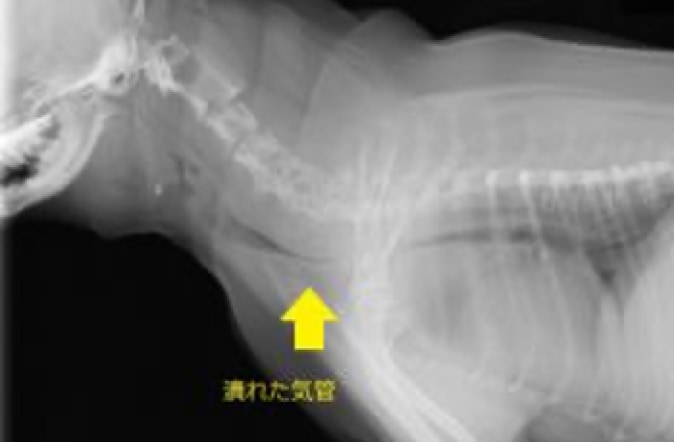

気道の狭さ:短頭種は、鼻や喉などの気道が短く、狭くなっています。これにより、空気の流れがスムーズでなくなり呼吸困難が生じます。具体的には鼻孔狭窄:鼻の入り口が狭くなり、空気の通りが悪くなります。軟口蓋過長:口の奥にある軟らかい部分(軟口蓋)が長すぎて、気道を塞いでしまいます。喉頭の問題:喉の部分の腫れにより狭くなる場合があります。症状としては、呼吸時のいびきやうめき、運動後の呼吸困難や息切れ、嘔吐や咳などがみとめられます。治療は、体重管理:適切な体重を維持することで、気道への負担を軽減します。環境管理:過熱やストレスを避け、快適な環境を提供します。外科手術:重症の場合には、軟口蓋を短くする手術や、他の気道の問題を修正する手術が考慮されることがあります。